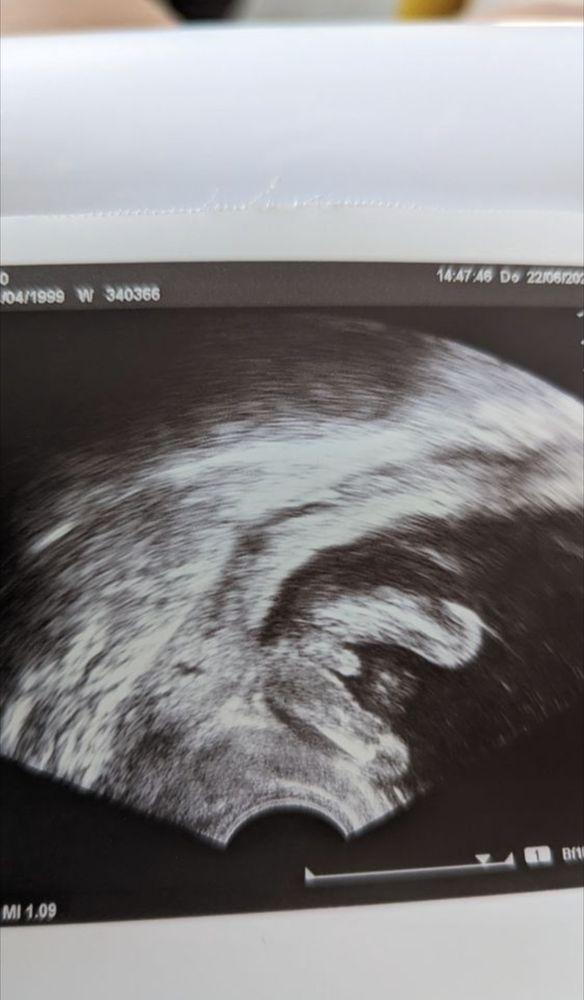

Какой пол?)

Вроде мальчик

Мальчик) Наглядно для тех кто говорит… что на двенадцатой неделе нельзя понять какой пол у ребёнка) просто не всегда так удачно можно поймать

Изображение На том же сроке, тот же ракурс - мальчик🩵 все дальнейшие УЗИ и скрининги подтвердили)

Мальчик 💙

Видно ли кто? Мальчик или девочка? Может кто нибудь может определить кто тут у нас девочка или мальчик по своему опыту